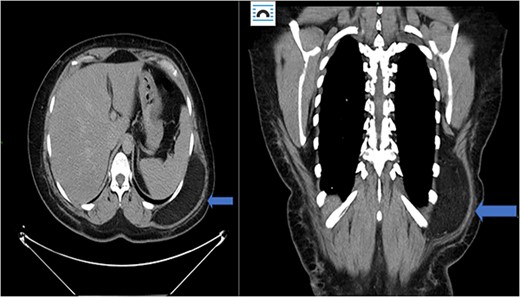

In the emergency department, vital signs were remarkable for elevated blood pressure of 166/81, but otherwise stable and afebrile. WBC count was elevated at 15.4 with left shift and hemoglobin was low at 9.6. Complete Metabolic Panel was notable for hyponatremia of 128, and mildly elevated BUN/serum creatinine of 26/1.5 which was slightly higher than his baseline of 17/1.3. Liver function tests were unremarkable. UA showed likely UTI with positive esterase, high RBC/WBC and bacteria and protein. A CT of the abdomen and pelvis was done, showing a left non-obstructing kidney stone and a left retroperitoneal fat density with stranding along the left iliopsoas measuring 12.6 × 8.1 cm × 3.7 cm, which was described as possibly a part of infectious or malignant process (Fig. 5). Subsequently, patient’s prior CT scans were available to be reviewed and it showed the same lipomatous mass 9 years earlier. (Fig. 6). Given the patient’s symptoms of left lower extremity pain and the possibility that the mass was responsible, a CT-guided core biopsy was ordered for diagnosis to rule out a malignant process as operative intervention was being contemplated. Pathology report of the core biopsy showed lobules of univacuolated adipocytes divided by thin septa. There were frequent multivacuolated adipocytes with small round nuclei, reminiscent of brown fat cells. No enlarged hyperchromatic cells, mitotic figures nor necrosis are seen. The findings supported the diagnosis of the lipoma variant of hibernoma (Fig. 4). Given the chronicity of the mass, the near identical size over 9 years and the diagnosis made from core biopsy, it was determined that the hibernoma was not the likely source of the patient’s LLE pain and hence the mass was not excised.